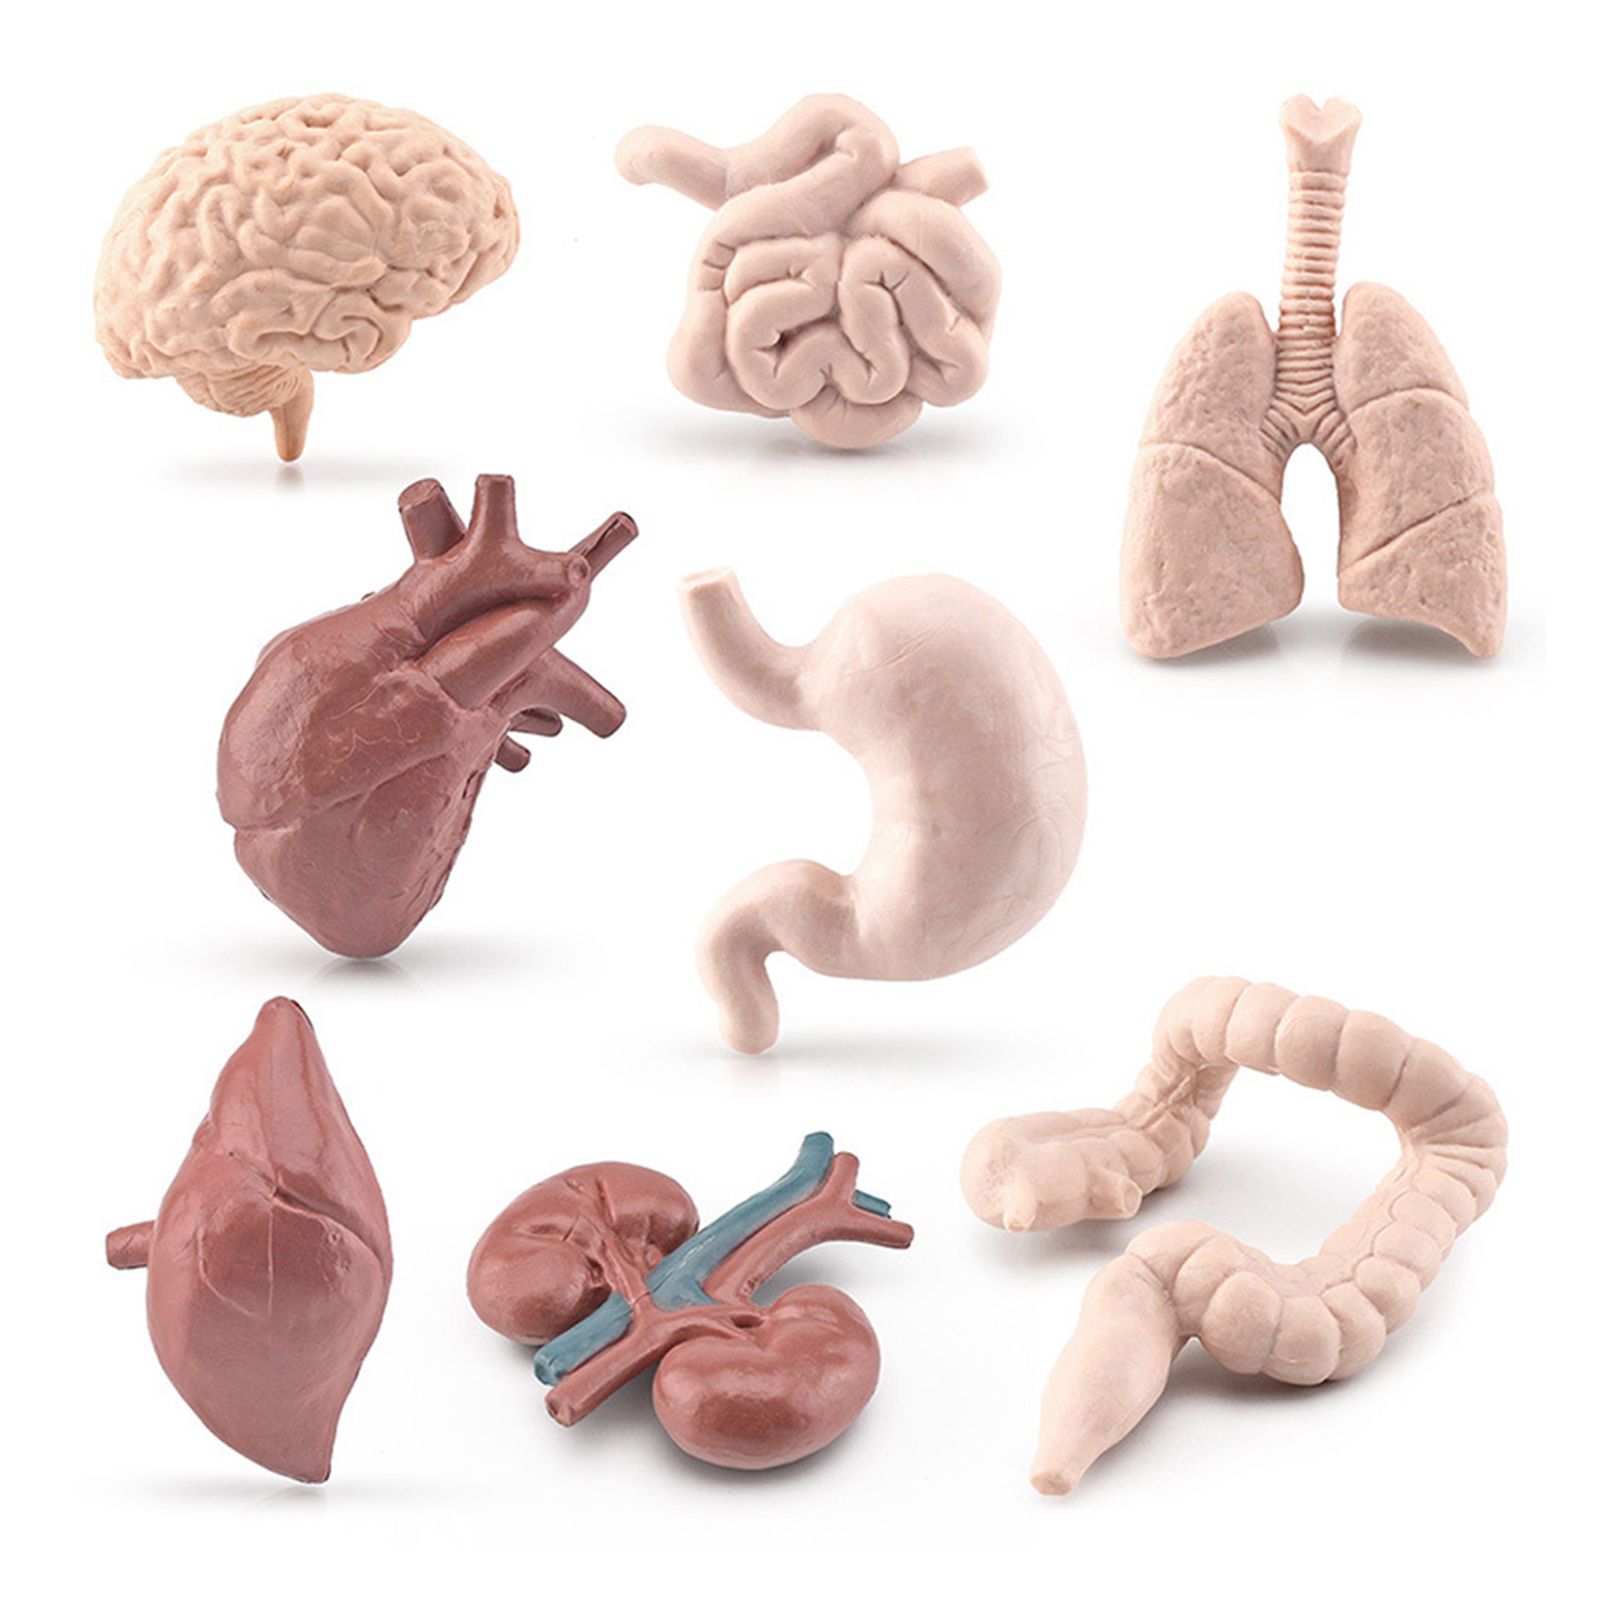

Анатомия желудка и сердца: визуализация и изучение

Раздел: Фотопанорама